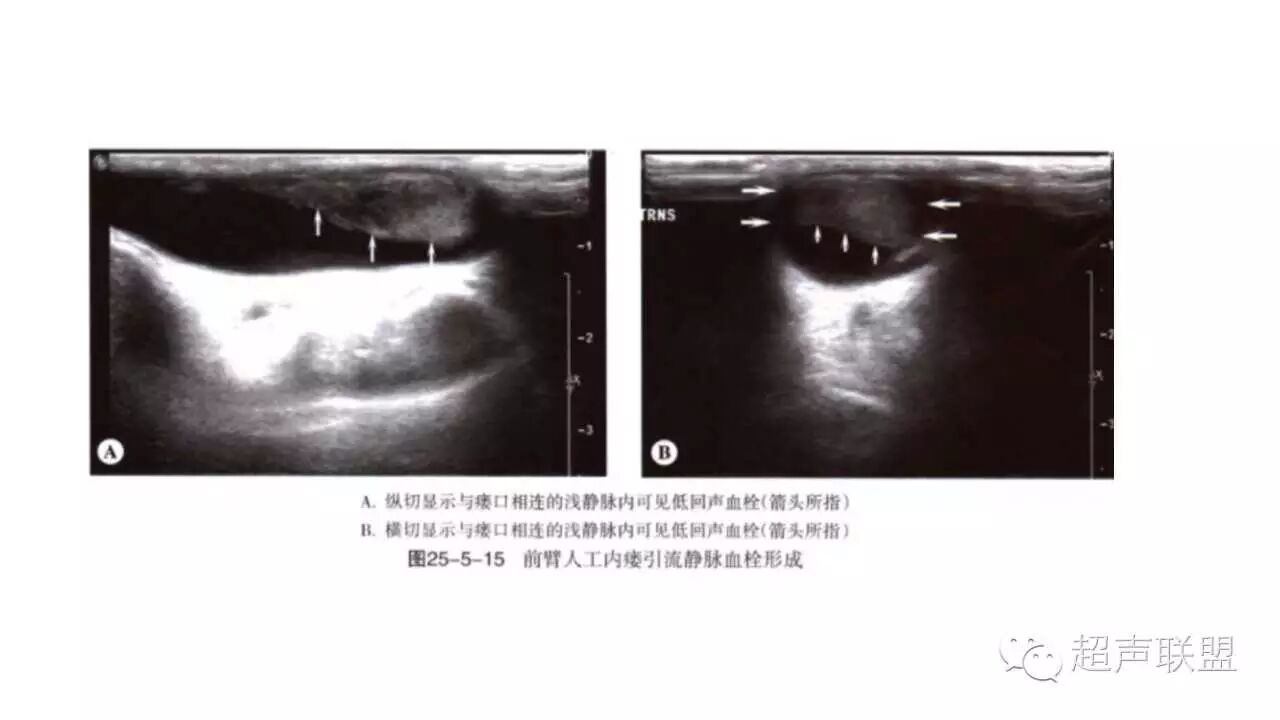

2、血栓与闭塞:

血栓与狭窄密切相关,常发生于静脉侧,静脉管腔完全压瘪可除外血栓形成。

闭塞处可见血流信号中断,多普勒血流信号消失。供血动脉血流呈高阻频谱改变。